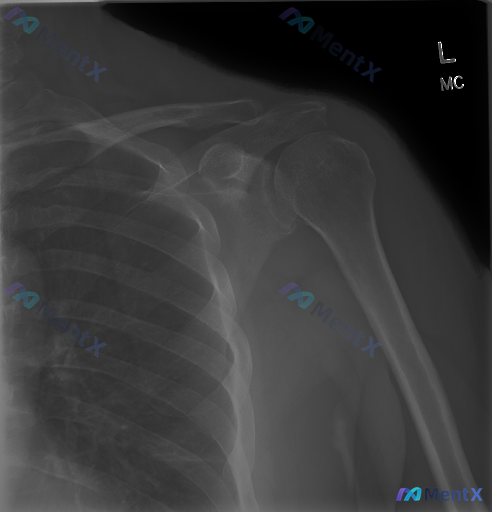

整理到一份左侧肩部的影像资料: - 只有正位X光片,报告写得很明确:左侧肩关节结构完整,对位好,没有骨折、脱位、骨赘、钙化斑块,也没有明显的退变或骨质破坏。 - 但同时有个提示说「存在异常」——意味着可能有临床症状或者其他预设信息,但影像上没直接看到。 大家遇到这种「影像阴性但临床高度怀疑有问题」的...